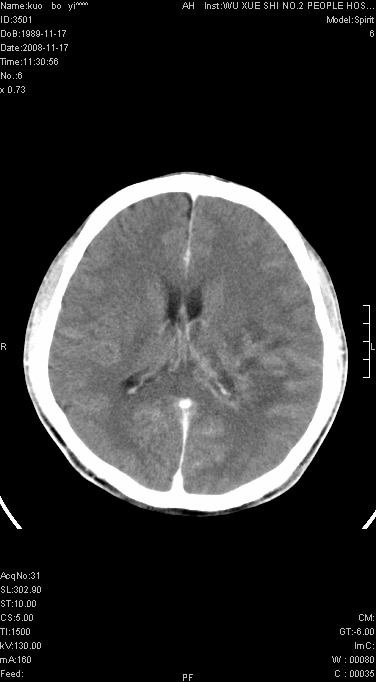

增强已传.年龄19岁.请会诊

增强后水肿中心高密度灶有明显强化,强化不均匀,呈雪花状或絮状,且强化明显,若为肿瘤,应该出现形态较规则的瘤体影,强也有例外如胶质瘤就可以形态不规则.但胶质瘤明显强化者多为恶性间变性,与病史及相关表现太不相符.因此本例多考虑为炎症引起.

左顶叶较大范围水肿区,内见明显强化的片状 棉絮状组织,但占位效应不明显。多考虑:脑炎!

还是考虑原发脑胶质瘤,梗塞缺血水肿的低密度要同时累及皮、髓质并要符合动脉供血的区域分界特点,本例强化后见瘤体结节及向周围浸润生长的瘤血管都强化了,水肿广泛呈指状,占位效应使同侧脑皮质受压变薄、脑沟消失但因实质性的瘤体尚小所以中线无明显移位。不知各位同意这样分析吗?(转移瘤多为多处病灶)